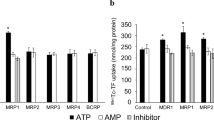

To measure ABCB1 function in chemotherapy-resistant tumors, we imaged three groups of mice with [18F]AVT-011 before and after tariquidar treatment (Fig. 3a, b) and with [18F]FDG for anatomical localization. Wild-type mice were implanted orthotopically with breast tumors comprising three levels of Abcb1a/b expression and ABCB1 protein levels (Supplemental Fig. 2) found in clinical tumors [1]: basal, intermediate (3-fold increase in Abcb1a/b), or high (~ 521-fold increase in Abcb1a/b). These tumor grafts were derived from Brca1−/−;p53−/− mouse breast tumors that were previously responsive to chemotherapy (basal) or developed resistance after several cycles of treatment with doxorubicin (intermediate) or with pegylated liposomal doxorubicin [26]. After injection of [18F]AVT-011, radioactivity concentrations (%ID/g) in tumors peaked within the first 5 min and reached a plateau by 45 min (Fig. 3c, d). Tumor uptake of [18F]AVT-011, measured as AUC of %ID/g*min from 5–42.5 min, was 15% lower in the intermediate group (Padj = 0.10) and 32% lower in the high ABCB1–expressing group (P < 0.001) than in the basal group (Fig. 4a). In contrast, tumor uptake of [18F]FDG, measured as %ID/g at 60 min after injection, was not significantly different among the three groups (intermediate vs basal, Padj = 0.92; high vs basal, Padj = 0.16; Fig. 4b).

[18F]AVT-011 can discriminate tumors expressing basal and high levels of ABCB1, while [18F]FDG cannot. a Tumor uptake of [18F]AVT-011, measured as the area under the curve of %ID/g from 5 to 42.5 min, in tumors expressing basal (n = 9), intermediate (n = 7), or high (n = 10) levels of ABCB1. b Tumor uptake of [18F]FDG, measured as %ID/g at 60 min after injection, in the same tumors imaged 1 day prior to [18F]AVT-011. ***P < 0.001 by one-way ANOVA followed by Dunnett’s multiple comparisons test

Radioactivity concentrations in the tumor increased in all groups following a bolus injection of tariquidar (15 mg/kg) administered 45 min after injection of [18F]AVT-011 (Fig. 3c). Relative to tumor uptake at 45 min, tumor uptake (%ID/g) at 90 min increased by 27.5 ± 9.7% in the basal group, by 31.2 ± 13.3% in the intermediate group, and by 40.9 ± 3.7% in the high ABCB1–expressing group. The percentage increase in the high ABCB1–expressing group was significantly higher than in the basal group (Padj = 0.02). By contrast, the increase in tumor uptake between 45 and 90 min in animals not treated with tariquidar (Fig. 3d) was 10.4 ± 10.6% in the basal group (n = 4 mice) and 5.4 ± 12.6% in the high ABCB1–expressing group (n = 5 mice). The percentage increase in muscle uptake (%ID/g) at 90 min after radiotracer injection relative to muscle uptake at 45 min (before tariquidar administration) was not significantly different between animals injected with tariquidar mid-scan (24.1 ± 5.0 %) and those not injected with tariquidar mid-scan (29.1 ± 2.9%, Supplemental Fig. 3). At the end of the scan (i.e., at 90 min), intact [18F]AVT-011 in mouse plasma was 83.8 ± 1.9% in the basal group, 54.1 ± 14.8% in the intermediate group (Padj = 0.02), and 85.7 ± 2.6% in the high ABCB1–expressing group (Padj = 0.83).